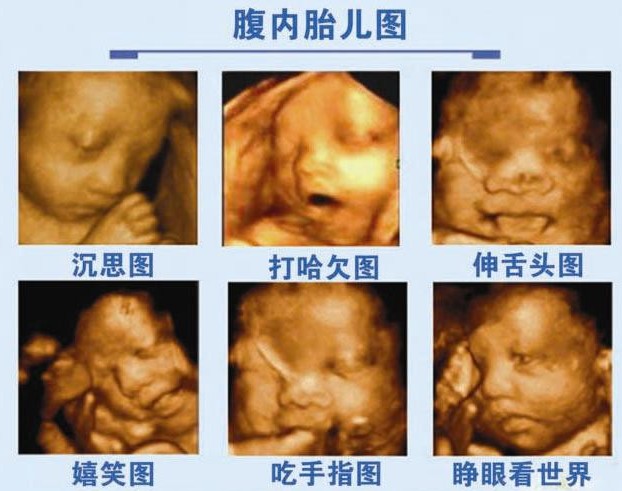

3、可视: 高清四维能自动为胎儿拍摄宫内"写真"和动态录像,不再是仅仅感觉宝宝的呼吸和运动,而且可以亲眼目睹肚子里宝宝的乖巧容貌和可爱动作,为准妈妈增添了不少情趣.让准妈妈有一个愉快舒畅的心情.

一、四维彩超系统不但可以拍摄极为细致的立体、连动的影像,让准爸爸、妈妈亲眼看见胎儿的实时动态,而且能直接检测胎儿的四肢及内脏,立体显示胎儿各器官的发育情况,对尚在孕妇腹中的胎儿颜面部的清晰显示,更可以jing确筛查腹中胎儿所患的如唇腭裂等非常细小的畸形.